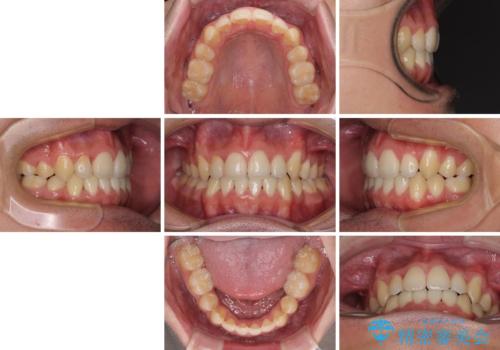

- 上下の八重歯や乱杭歯を気にして来院され患者様です。

スペースを確保するため、上下左右の小臼歯を抜歯し、ワイヤー装置に矯正することとしました。

奥歯の咬み合わせの左右差が大きかったため、変則的な抜歯矯正を行いました。

治療期間はやや長期化しましたが、満足のいく歯並びとなりました。